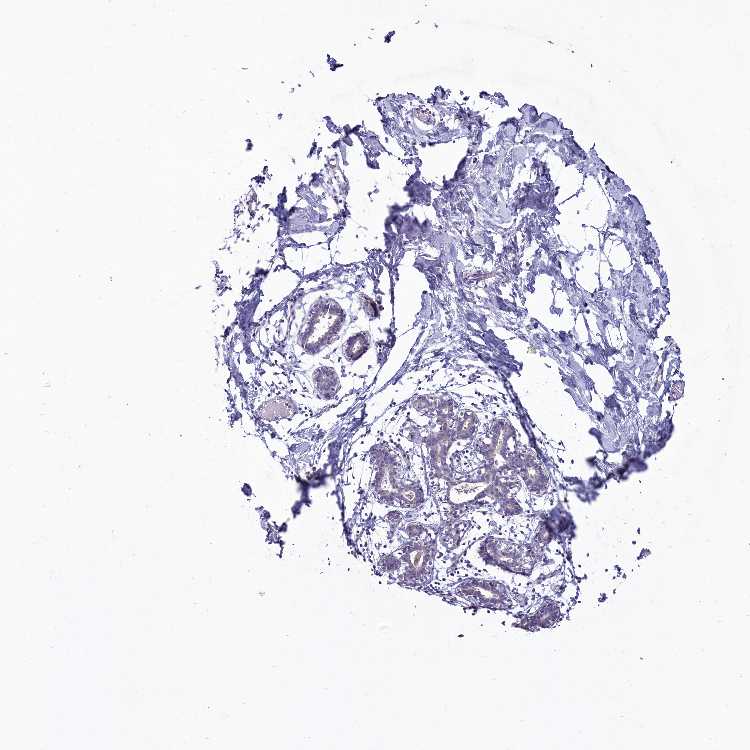

BREAST - Antibody stainingi

Antibody staining in the annotated cell types in the current human tissue is reported as not detected, low, medium, or high, based on conventional immunohistochemistry profiling in selected tissues. This score is based on the combination of the staining intensity and fraction of stained cells.

Each image is clickable and will lead to virtual microscopy that enables deeper exploration of all samples and also displays staining intensity scores, fraction scores and subcellular localization as well as patient and tissue information for each sample.

Antibody HPA043059

Adipocytes Not detected

Glandular cells Not detected

Myoepithelial cells Not detected